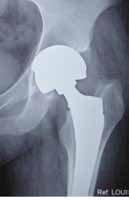

S-Rom style modular junction is that of a taper between the stem body and internal portion of the sleeve.

The Apex Modular™ Stem is the shape of a S-Rom style stem consisting of a circular fl uted distal stem with a proximal cone and medial triangle. The difference is in the ability to independently choose stem size, neck offset, version angles, and head size. The Apex Modular™ system allows surgeons to precisely address patient specifi c anatomical needs to achieve accurate leg length and soft tissue balance with the proximal neck/shoulder modularity. The proximal end of each stem includes an alignment pin that engages with the mating hole on the distal surface of each neck. Neutral necks have a single hole; anteversion necks have two holes for +/- 13° . This ability to adjust neck orientation eliminates the need for separate left and right stems, thus reducing inventory requirements, while enabling better restoration of joint biomechanics. The pin and hole also provide additional torsional stability, as well as control of the version angle.